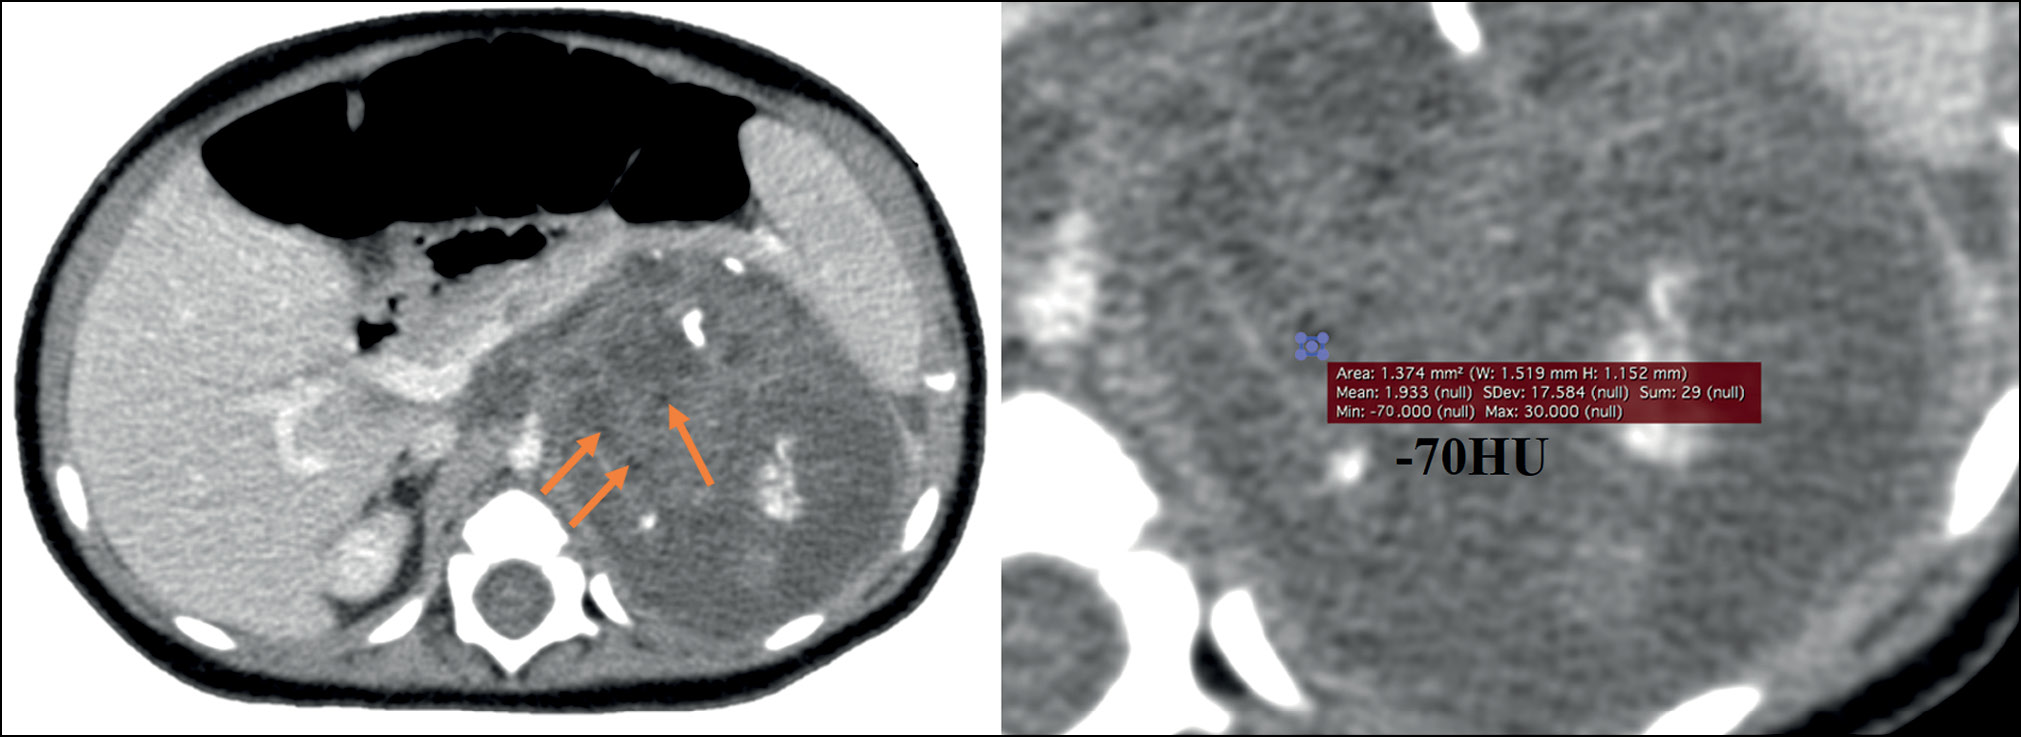

September 23, 2020: A contrast-enhanced abdominal multislice computed tomography (MSCT) revealed a retroperitoneal space-occupying mass on the left, measuring 81 × 71 × 87 mm (volume: 260 cm3), with a heterogeneous structure incorporating areas of calcification and inclusion cysts; the contrast uptake was weak. The neoplasm extended to the renal sinus area, without discernible signs of extension into the renal parenchyma. The adrenal gland extended across the lateral contour. The renal vessels on the left side followed the tumor contour; the superior mesenteric artery was displaced to the right, while the celiac artery was displaced upward (Fig. 1).

Fig. 1. Initial abdominal computed tomography using intravenous contrast dated September 23, 2020, a pattern of a space-occupying retroperitoneal mass on the left: (a) axial plane; the arrow indicates the displacement of the superior mesenteric artery to the right; (b) axial plane; (c) sagittal plane; the arrow indicates the upward displacement of the celiac artery; (d) coronal plane; the arrow indicates the tumor extension into the renal sinus.

This case report underscores the need to thoroughly examine the tumor node structure and assess the density of different tumor components. The retrospective examination of the diagnostic errors revealed that teratoma could have been suspected as early as the initial abdominal MSCT, as the presence of small hypodense inclusions (–70 HU) consistent with the lipid component of the tumor and uncharacteristic of neuroblastoma should have been considered (Fig. 6).

Fig. 6. Initial contrast-enhanced abdominal computed tomography dated September 23, 2020, axial plane. Arrows indicate small hypodense areas of the tumor, with a density of −70 HU.